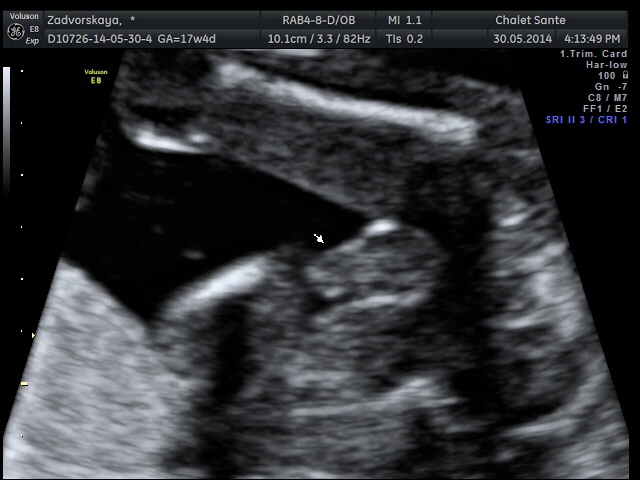

У нас сынок)))

Вопросы про УЗИ, обследования и анализы: что, где, как, когда?Девочки гляньте, это же мальчик??))) врач говорит 100% мальчуган, муж поверить не может своему счастью!!!))))

Стрелочки указывают на писюн))) нам все показали и рассказали, про все все органы и части тела, я оч довольна, бесплатное узи это конечно для врачей больше информация, а тут все рассказывают, показывают)))) нам оч понравилось)